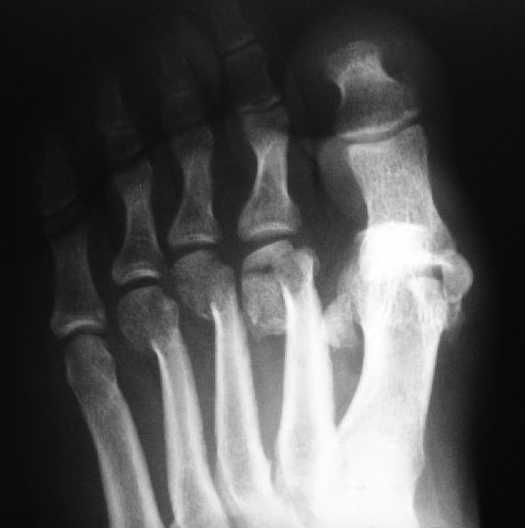

1 передний отдел стопы делается в косой, а не боковой проекции - на боковой все плюсневые кости накладываются друг на друга, и ничего не видно - это же аксиоматично! Я, например, на прямых проекциях не вижу совсем признаков перелома первой и четвертой плюсневой, и сомневаюсь в переломе третьей, боковые же совершенно неинформативны.

Как же суть проблемы видна? Человек говорит о переломе первой (то есть речь идет о переломо-вывихе?), второй, третьей и четвертой плюсневых костей, а я вижу только перелом второй. мне кажется, что проблема в таком случае будет чуть-чуть другая. Кстати, сколько переломов насчитали на этих снимках Вы?

Однозначно-переломы 1,2,3,4 плюсневых костей.

Не знаю, что за проблема, но я на своем мониторе переломы отлично вижу.

Та же проблема - по крайней мере на снимке в аппарате (фас) отчетливо видно перелом ее головки.